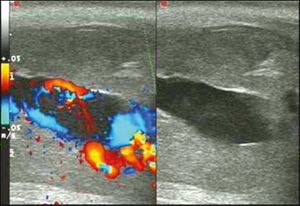

Blood gas testing the blood from the cavernosa of the penis can help in the diagnosis.[3] If the low-flow type of priapism is present, the blood typically has a low pH, while if the high-flow type is present, the pH is typically normal.[3] Color Doppler ultrasound may also help differentiate the two.[3] Testing a person to make sure they do not have a hemoglobinopathy may also be reasonable.[3]

Ultrasonography

Color Doppler ultrasound demonstrating a hypoechoic collection that corresponds to hematoma with arteriovenous fistula secondary to traumatic injury of the penis due to impact with bicycle handlebars, resulting in high-flow priapism[11]

Penile ultrasonography with Doppler is the imaging method of choice, because it is noninvasive, widely available, and highly sensitive. By means of this method, it is possible to diagnose priapism and differentiate between its low- and high-flow forms.[11]

In low-flow (ischemic) priapism the flow in the cavernous arteries is reduced or absent. As the condition progresses, there is an increase in echogenicity of the corpora cavernosa, attributed to tissue edema. Eventually, changes in the echotexture of the corpora cavernosa can be observed due to the fibrotic transformation generated by tissue anoxia.[11]

In high-flow priapism normal or increased, turbulent blood flow in the cavernous arteries is seen. The area surrounding the fistula presents a hypoechoic, irregular lesion in the cavernous tissue.[11]